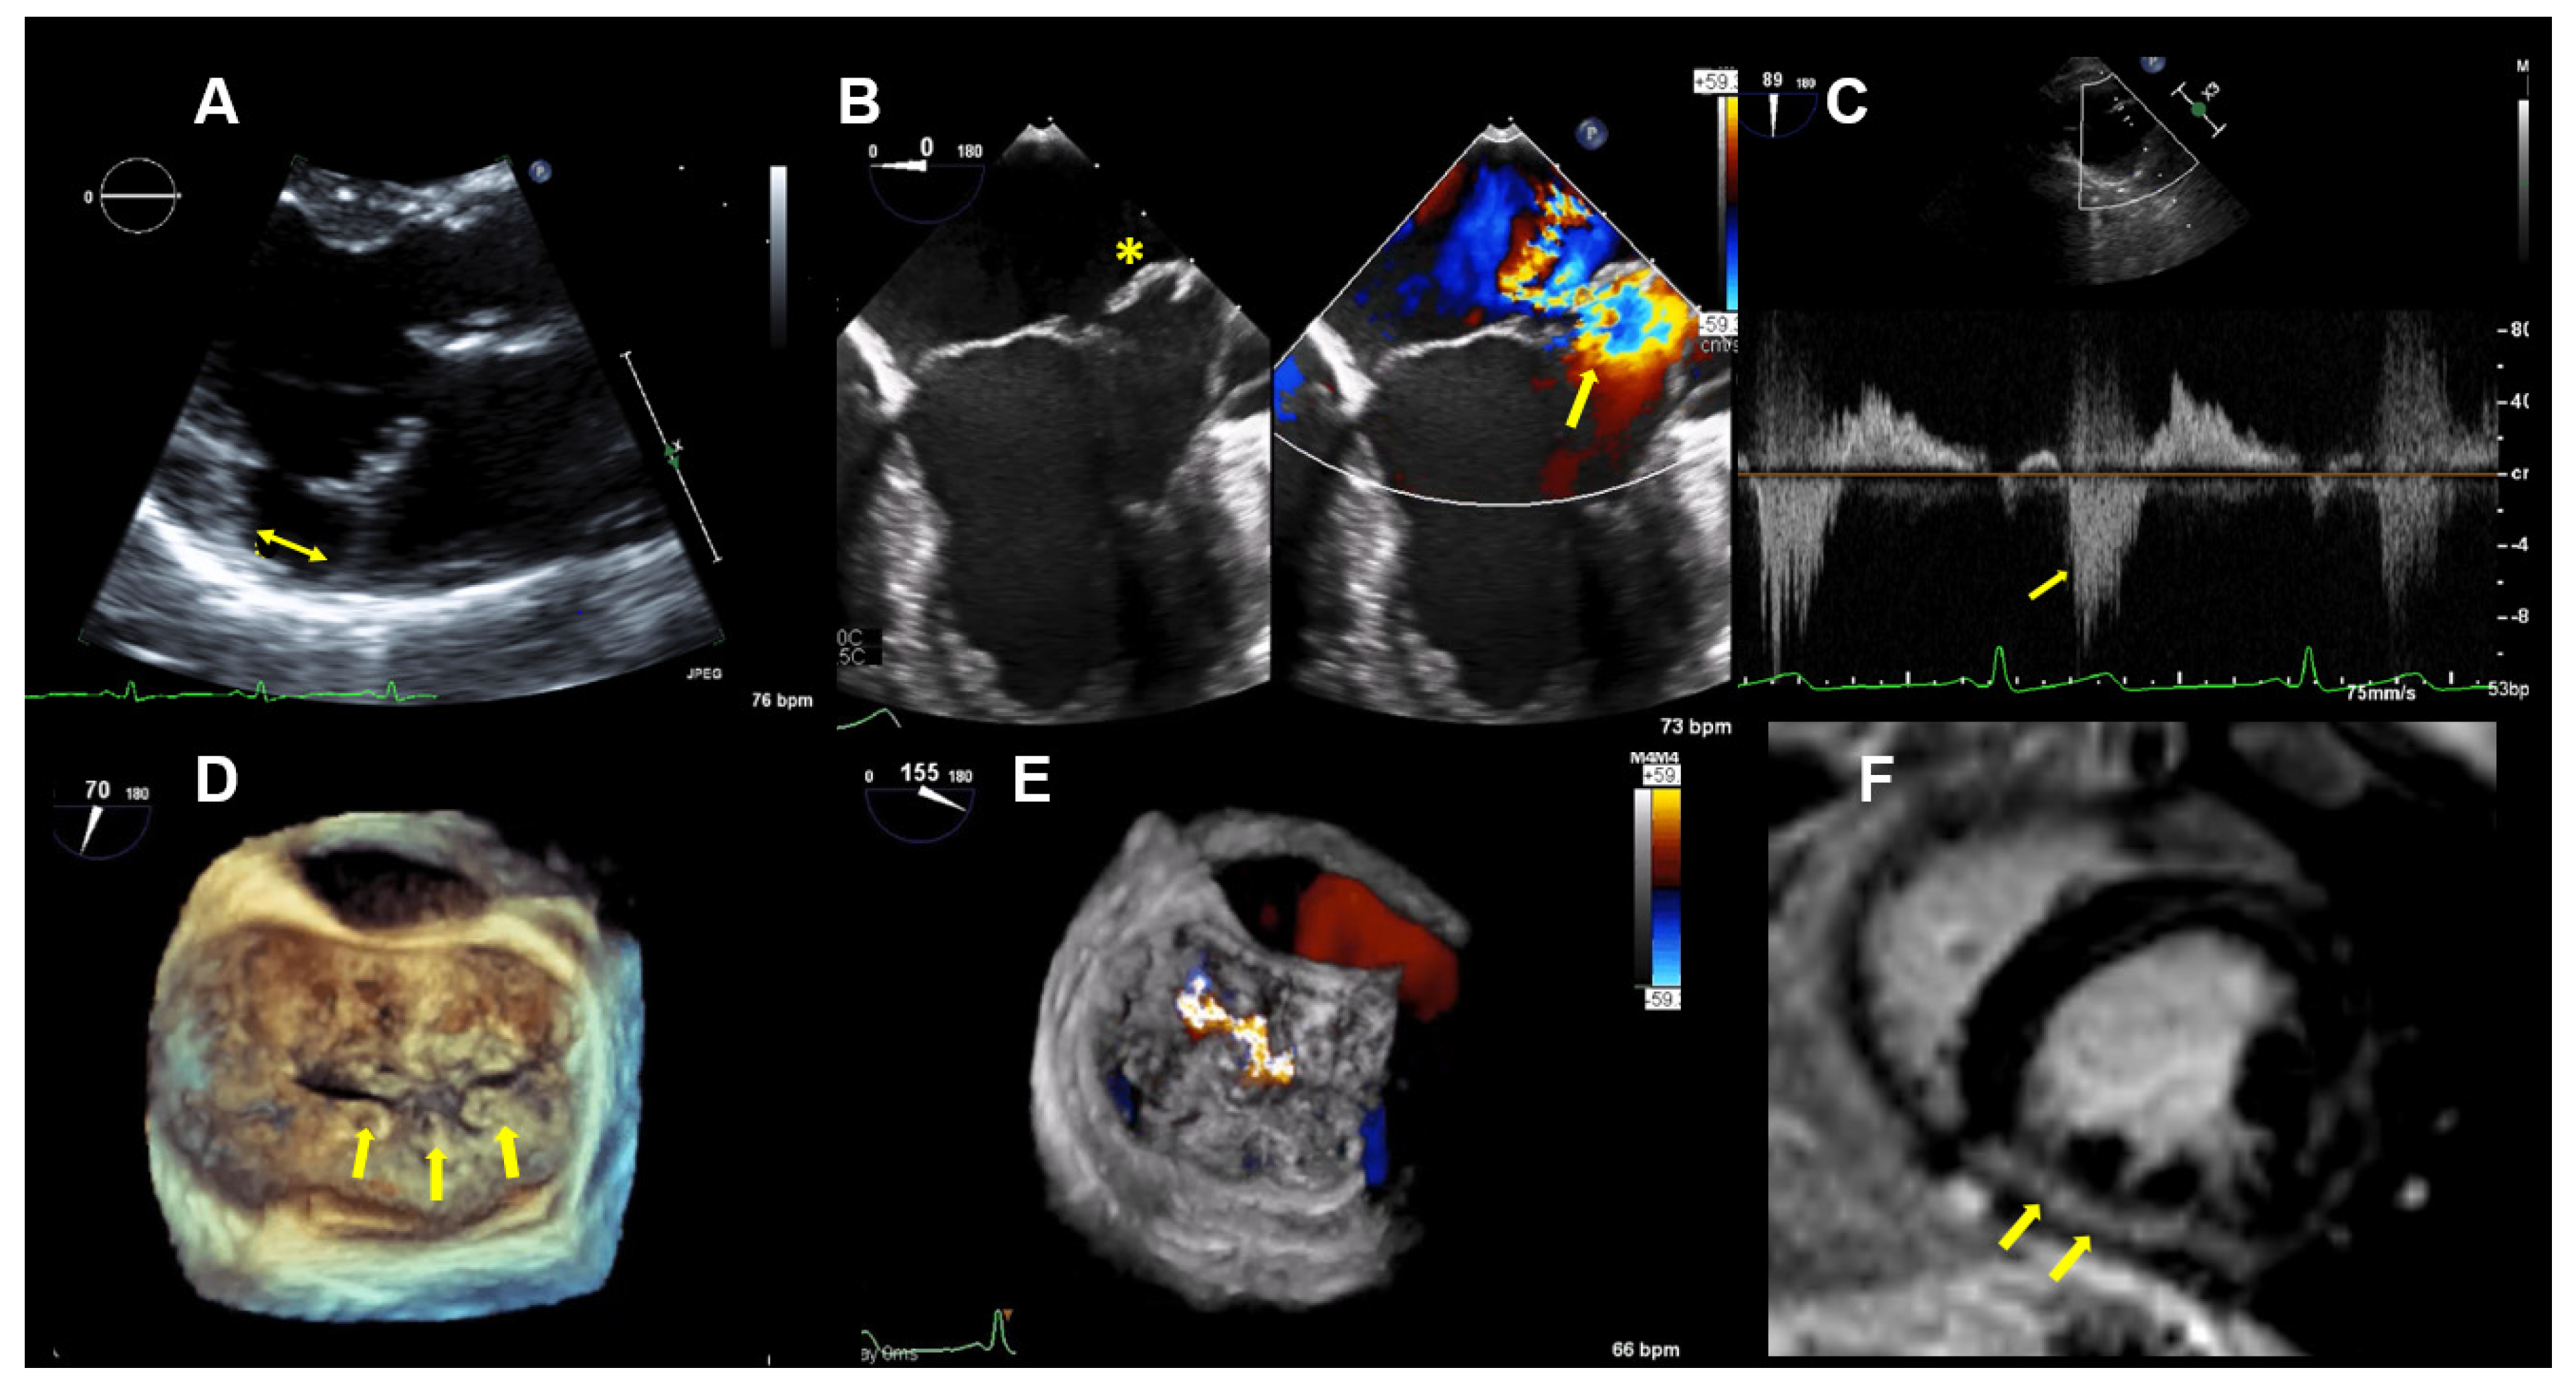

Figure 3.

Case 2: Summary of the key findings from multimodality imaging. (A) The mitral annular disjunction (yellow double arrow) is visualized in a 3D transthoracic echocardiography view. (B) A 4-chamber transesophageal echocardiographic (TEE) view shows the bi-leaflet prolapse, which is more pronounced in the posterior leaflet (yellow asterisk), thus resulting in an eccentric mitral regurgitation (MR) jet, as seen in color Doppler (right; yellow arrow). (C) The pulsed-wave Doppler profile derived in the left superior pulmonary vein shows a reverse systolic flow (yellow arrow) as a sign of severe MR. (D) Larger prolapse segments are marked with a yellow arrow in a 3D TEE view. (E) The MR is seen in a 3D TEE enface view with color Doppler. (F) Cardiac magnetic resonance imaging reveals focal mid-wall and subendocardial fibrosis in the mid-inferior wall (yellow arrows).

This patient is a 46-year-old woman with known bi-leaflet prolapse and a known MAD. She has occasional palpitations and mild dyspnea on exertion but was able to function as a yoga and Pilates instructor. She had serial TTE examinations over a period of eight years to monitor her moderate MR. Over this time period, a reduction of the LVEF from 68% to 60% was observed, as well as a slight increase of the LV-end systolic diameter from 37 to 40 mm. Brain natriuretic peptide levels were in the normal range, with 89 pg/mL.

TTE and TEE imaging confirmed the diagnosis of a bi-leaflet prolapse with myxomatous changes of both mitral leaflets (Barlow’s disease) and significant MR (Figure 3). A Zio XT patch monitor (iRhythm Technologies, San Francisco, CA, USA) showed frequent PVCs, nonsustained ventricular tachycardia (nsVT), and supraventricular tachycardia (SVT). Betablocker therapy was initiated.

A stress echocardiography revealed above-average functional capacity. However, she had evidence of an impaired contractile reserve. Namely, she did not have an augmentation of her LVEF with exercise—the increase was <5% during maximal stress. The peak exercise systolic pulmonary artery pressure was 43 mmHg. There were no signs of a stress-related ischemia.

CMR imaging confirmed a mildly impaired LV function (LVEF 53%) and a regurgitant fraction of 45% consistent with moderate-severe MR. The extracellular volume fraction was 34% (normal limit <30%), consistent with diffuse myocardial fibrosis. Focal mid-wall and subendocardial fibrosis was observed in the mid-inferior wall (Figure 3F).